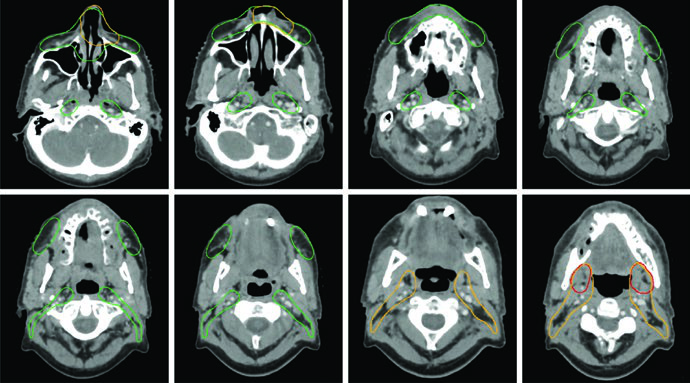

A simulação deve ser realizada com o paciente em decúbito dorsal, com suporte de cabeça e pescoço estendido, usando máscara termoplástica de cinco pontos (Aquaplast) que imobilize cabeça, pescoço e ombros. Uma prancha de tração de ombros pode ser utilizada para rebaixar os ombros fora do caminho do feixe.

Bloqueador de mordida ajuda a empurrar a língua inferiormente, afastando-a da nasofaringe de alta dose. Pacientes com muitas restaurações metálicas se beneficiam de um protetor bucal customizado para absorver elétrons secundários e reduzir a mucosite. A TC de simulação deve usar cortes de até 3 mm com contraste IV, cobrindo do vértice da cabeça até a carina. O isocentro fica tipicamente posicionado nas aritenoides.

Para casos pós-operatórios, marcadores radiopacos nas cicatrizes cirúrgicas auxiliam na delineação do leito tumoral. A guia por imagem diária — idealmente com cone beam CT (CBCT) alinhado ao osso — é fundamental. Imagens kV diárias com CBCT semanal também são adequadas.

A irradiação nodal eletiva deve ser considerada caso a caso. Linfonodos eletivos fazem sentido para ENB e carcinoma espinocelular avançado, especialmente quando a origem é o seio maxilar ou quando há envolvimento de áreas com suprimento linfático extenso — nasofaringe, mucosa, pele, bochecha, nariz anterior, gengiva maxilar ou crista alveolar.

A drenagem nodal regional segue padrões previsíveis: linfonodos retrofaríngeos e níveis IB–IV. O nível V deve ser incluído quando há envolvimento da nasofaringe. Cobertura de linfonodos faciais deve ser considerada para tumores da cavidade nasal. A maioria dos tumores primários são estruturas de linha média, justificando irradiação nodal bilateral. A exceção são cânceres do seio maxilar, que recebem irradiação nodal unilateral.

Para o planejamento propriamente dito, a equipe do Memorial Sloan-Kettering Cancer Center preconiza uma abordagem sequencial de cone-down. O plano inicial (30 frações) utiliza dose-painting para entregar 54 Gy (1,8 Gy/fração) às regiões subclínicas de baixo risco e 60 Gy (2 Gy/fração) às regiões subclínicas de alto risco. Em seguida, um plano cone-down (5 frações) entrega 10 Gy adicionais exclusivamente à doença macroscópica, totalizando 70 Gy em 35 frações.